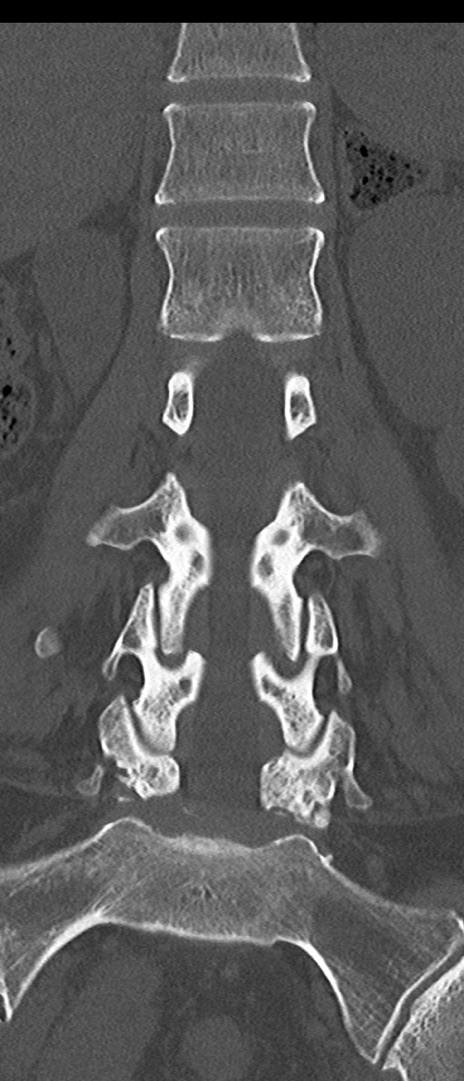

【整形】TIPS症例4 腰椎CT(冠状断像)

腰椎CT